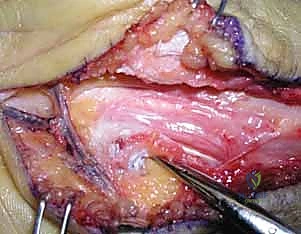

FIG 1 • C. The proximity of the motor branch of the ulnar nerve to the hook of the hamate as seen during excision of the hook.

Critical Note: Due to the motor branch's close proximity to the hook of the hamate, it is unfortunately easy to damage this nerve segment during excision of the hamate hook. Extreme caution is warranted.

- Deep Motor Branch (Zone 2): Carefully trace the deep motor branch as it dives dorsoradially. This is the segment most vulnerable during hamate hook excision. Ensure it is completely free of compression from any fibrous bands or the fibrous arch of the hypothenar muscles.

Surgical Warning: When excising the hook of the hamate (if indicated for fracture or impingement), extreme care must be taken to protect the deep motor branch of the ulnar nerve. It lies in very close proximity. Use fine instruments and visualize clearly. Consider using a small, curved osteotome or a rongeur, always protecting the nerve with a broad retractor.